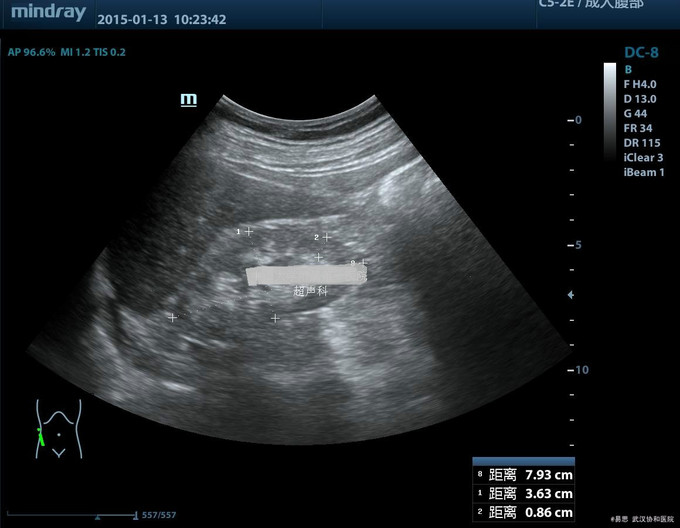

查体:BP:142/89mmHg。体型肥胖,无贫血貌;眼睑、颜面无浮肿。四肢关节无红肿压痛,足部小关节有畸形,活动欠佳。 辅查: 1.肌酐 276umol/L,尿酸UA 717umol/L;24小时尿蛋白定量:0.423g; 2.泌尿系统彩超:双肾萎缩,双肾慢性肾病声像图。